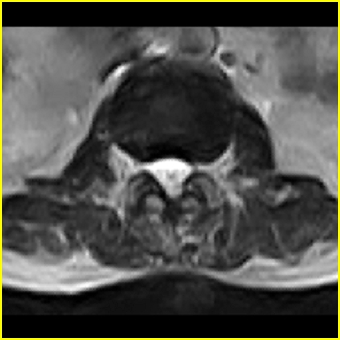

男,78岁,右下肢跛行两月.

右侧黄韧带肥厚或钙化,压迫马尾神经所致。必要时行ct扫描。

腰间盘膨出、黄韧带肥厚、可疑先天性腰椎管狭窄。

退行性病变:增生、椎间盘变性、膨出[l4-5、l5-s1 椎间盘膨出]

退行性骨关节病:增生、椎间盘变性、膨出..黄韧带肥厚.